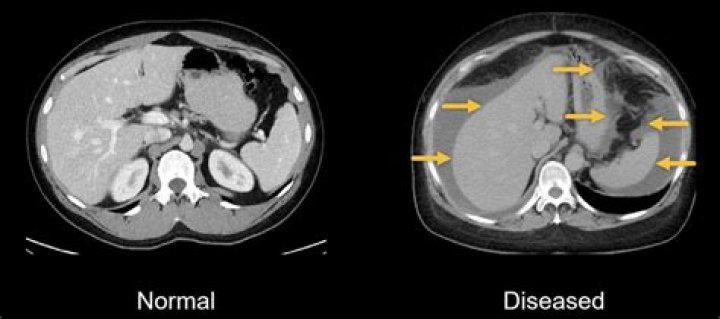

What is iliac artery stenosis?

Iliac artery disease is caused by the narrowing of the arteries leading to the legs. This narrowing can also be called stenosis. It is usually caused by a buildup of fat or calcium deposits called plaque. Over time, this plaque can build to a total blockage of the artery.